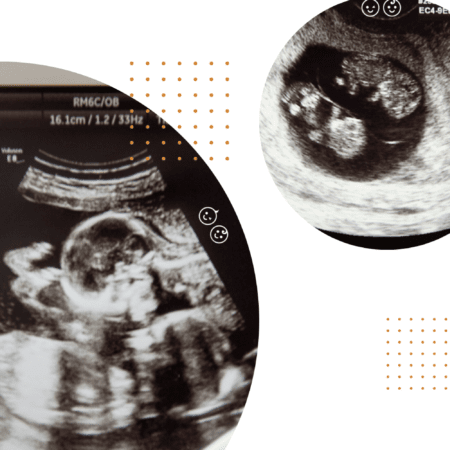

At your next twins ultrasound think about these top 10 tips for getting the most out of the visit. From twin ultrasound questions to finding out the sex.

Regardless of the type of twins you are having, you can be sure of one thing; you will be getting more ultrasounds than your friends had with their singletons. With so many twins ultrasound appointments ahead, there are some things you will want to know to make the most of these appointments and get all your questions and concerns addressed.

10. Ask for pictures

Ask the technician for print outs of the twins ultrasound pictures. These make a great addition to your twins’ baby books and pregnancy journal! Plus, what grandparent doesn’t want to see every picture they can get their hands on? The office will be happy to print them out for you at each appointment and some can even email them to you!